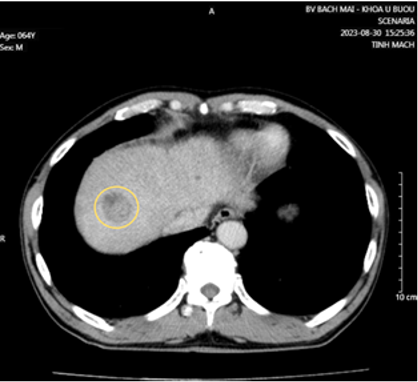

Cắt lớp vi tính ổ bụng có tiêm thuốc cản quang:

Hình 4: Theo dõi di căn hạch rốn gan (vòng tròn trắng).